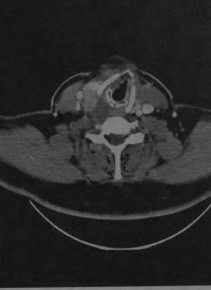

КТ с контрастированием : рак щитовидной железы на уровне щитовидного хряща справа. Опухоль имеет сложную структуру и включает зоны некроза, имеющие пониженную плотность, участки кровоизлияний, имеющие повышенную плотность и участки с интенсивным усилением после введения контраста. Опухоль смещает вперед гортань и нервно-сосудистый пучок. Кпереди от опухоли заметен дефект кожи.

КТ с контрастированием: обширное вертикальное распространение рака щитовидной железы в направлении головы. Опухоль содержит кистозные участки сниженной плотности, зоны кровоизлияний, имеющие повышенную плотность, и участки интенсивного усиления. В правой поднижнечелюстной области непосредственно кпереди от опухоли определяются крупные метастазы в лимфатические узлы.